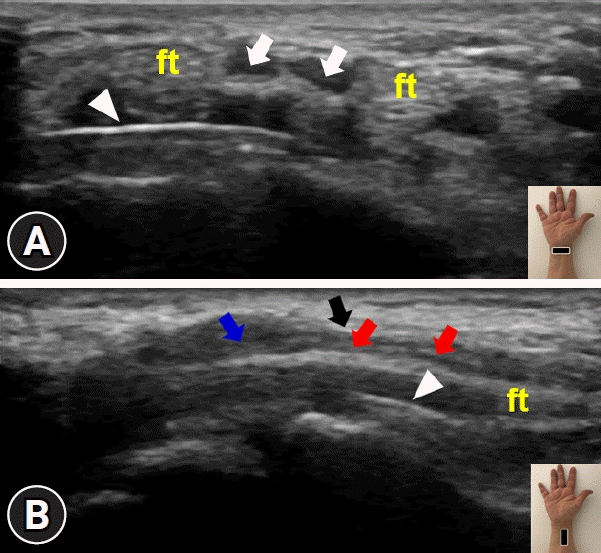

Supplementary Fig. 1.

Ultrasound imaging of the median nerve at the volar wrist. (A) Short-axis and (B) long-axis views show the median nerve (arrowheads) and metallic plate (arrows), which are located close to each other. Insets show the transducer’s position.